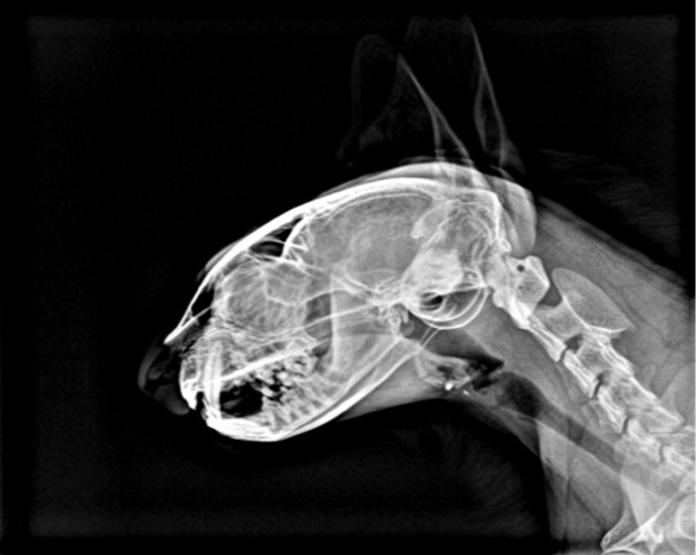

Se realizaron estudios radiográficos de dicha región, pruebas sanguíneas y urianálisis. Tanto la analítica sanguínea como el urianálisis estaban dentro de la normalidad. Al mismo tiempo, se realizó un Kit Elisa Test (prueba combinada SnapFeLV/FIV Idexx®) con resultando negativo. Las imágenes radiográficas craneales revelaron la presencia de un sobrecrecimiento calcificado e irregular, sin reacción perióstica, a la altura del arco cigomático derecho (Figura 1A-C).

Figura 1. Radiografías craneales, en posición (A) dorsoventral, (B) ventrodorsal y (C) laterolateral respectivamente, en la que se puede observar la presencia de una masa calcificada a la altura del arco cigomático.